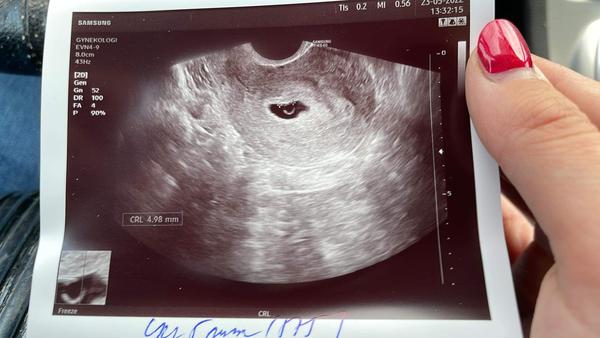

Dnes jsem byla u paní dr, udělala mi UTZ a tam mi řekla, že to vypadá spíš na 5+5tt. Pozvala mě za 3 týdny na další kontrolu a nic víc mi k tomu moc neřekla.

@evunka27 ale ten obrázek z ultrazvuku máte hezčí než já ,řekla bych že to bude v pořádku ❤️🍀

Děsíte mě ale zároveň i uklidňujete :D doktorka neříkala nic negativního, jen že bych měla ovulaci až někdy kolem 26.4 což si myslím, že byla o týden dřív, ale bůh ví, za jak dlouho se vajíčko uhnízdilo apod. Četla jsem právě tady na koníkovi, že to je běžné mít menší embryo.